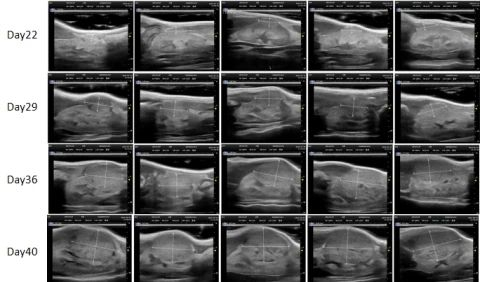

PDX Model (Growth Curve)

²¿·ÖÃÀ¸ß÷PDXÔλģ×Óչʾ